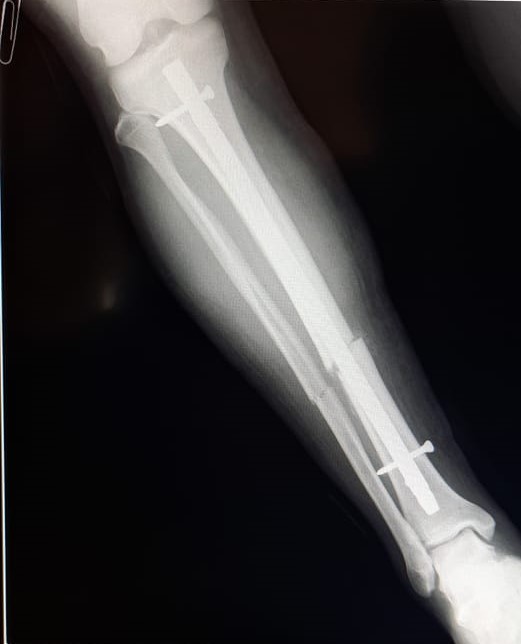

Se efectuó importante intervención quirúrgica en el

Se realizó una osteosíntesis endomedular de pierna derecha a un hombre de 35 años